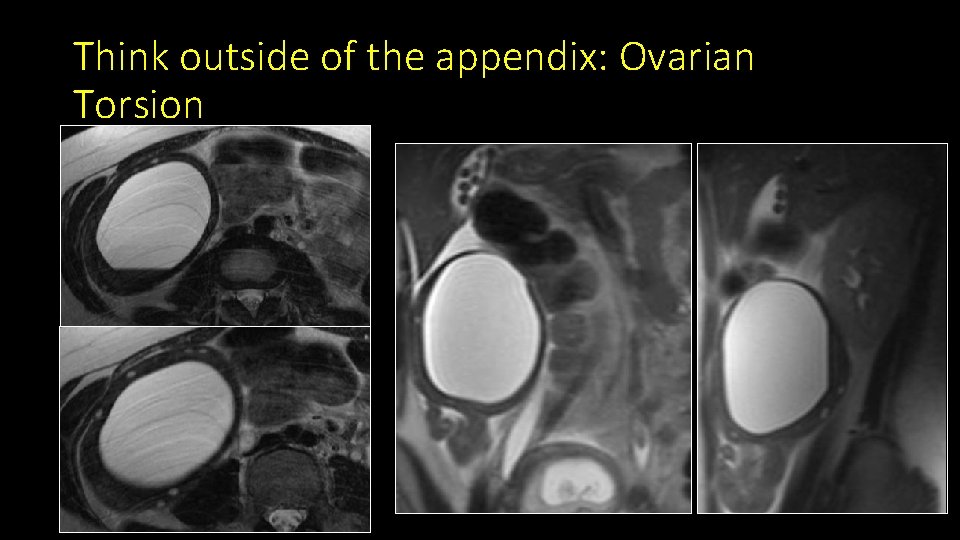

Think outside of the appendix: Ovarian Torsion